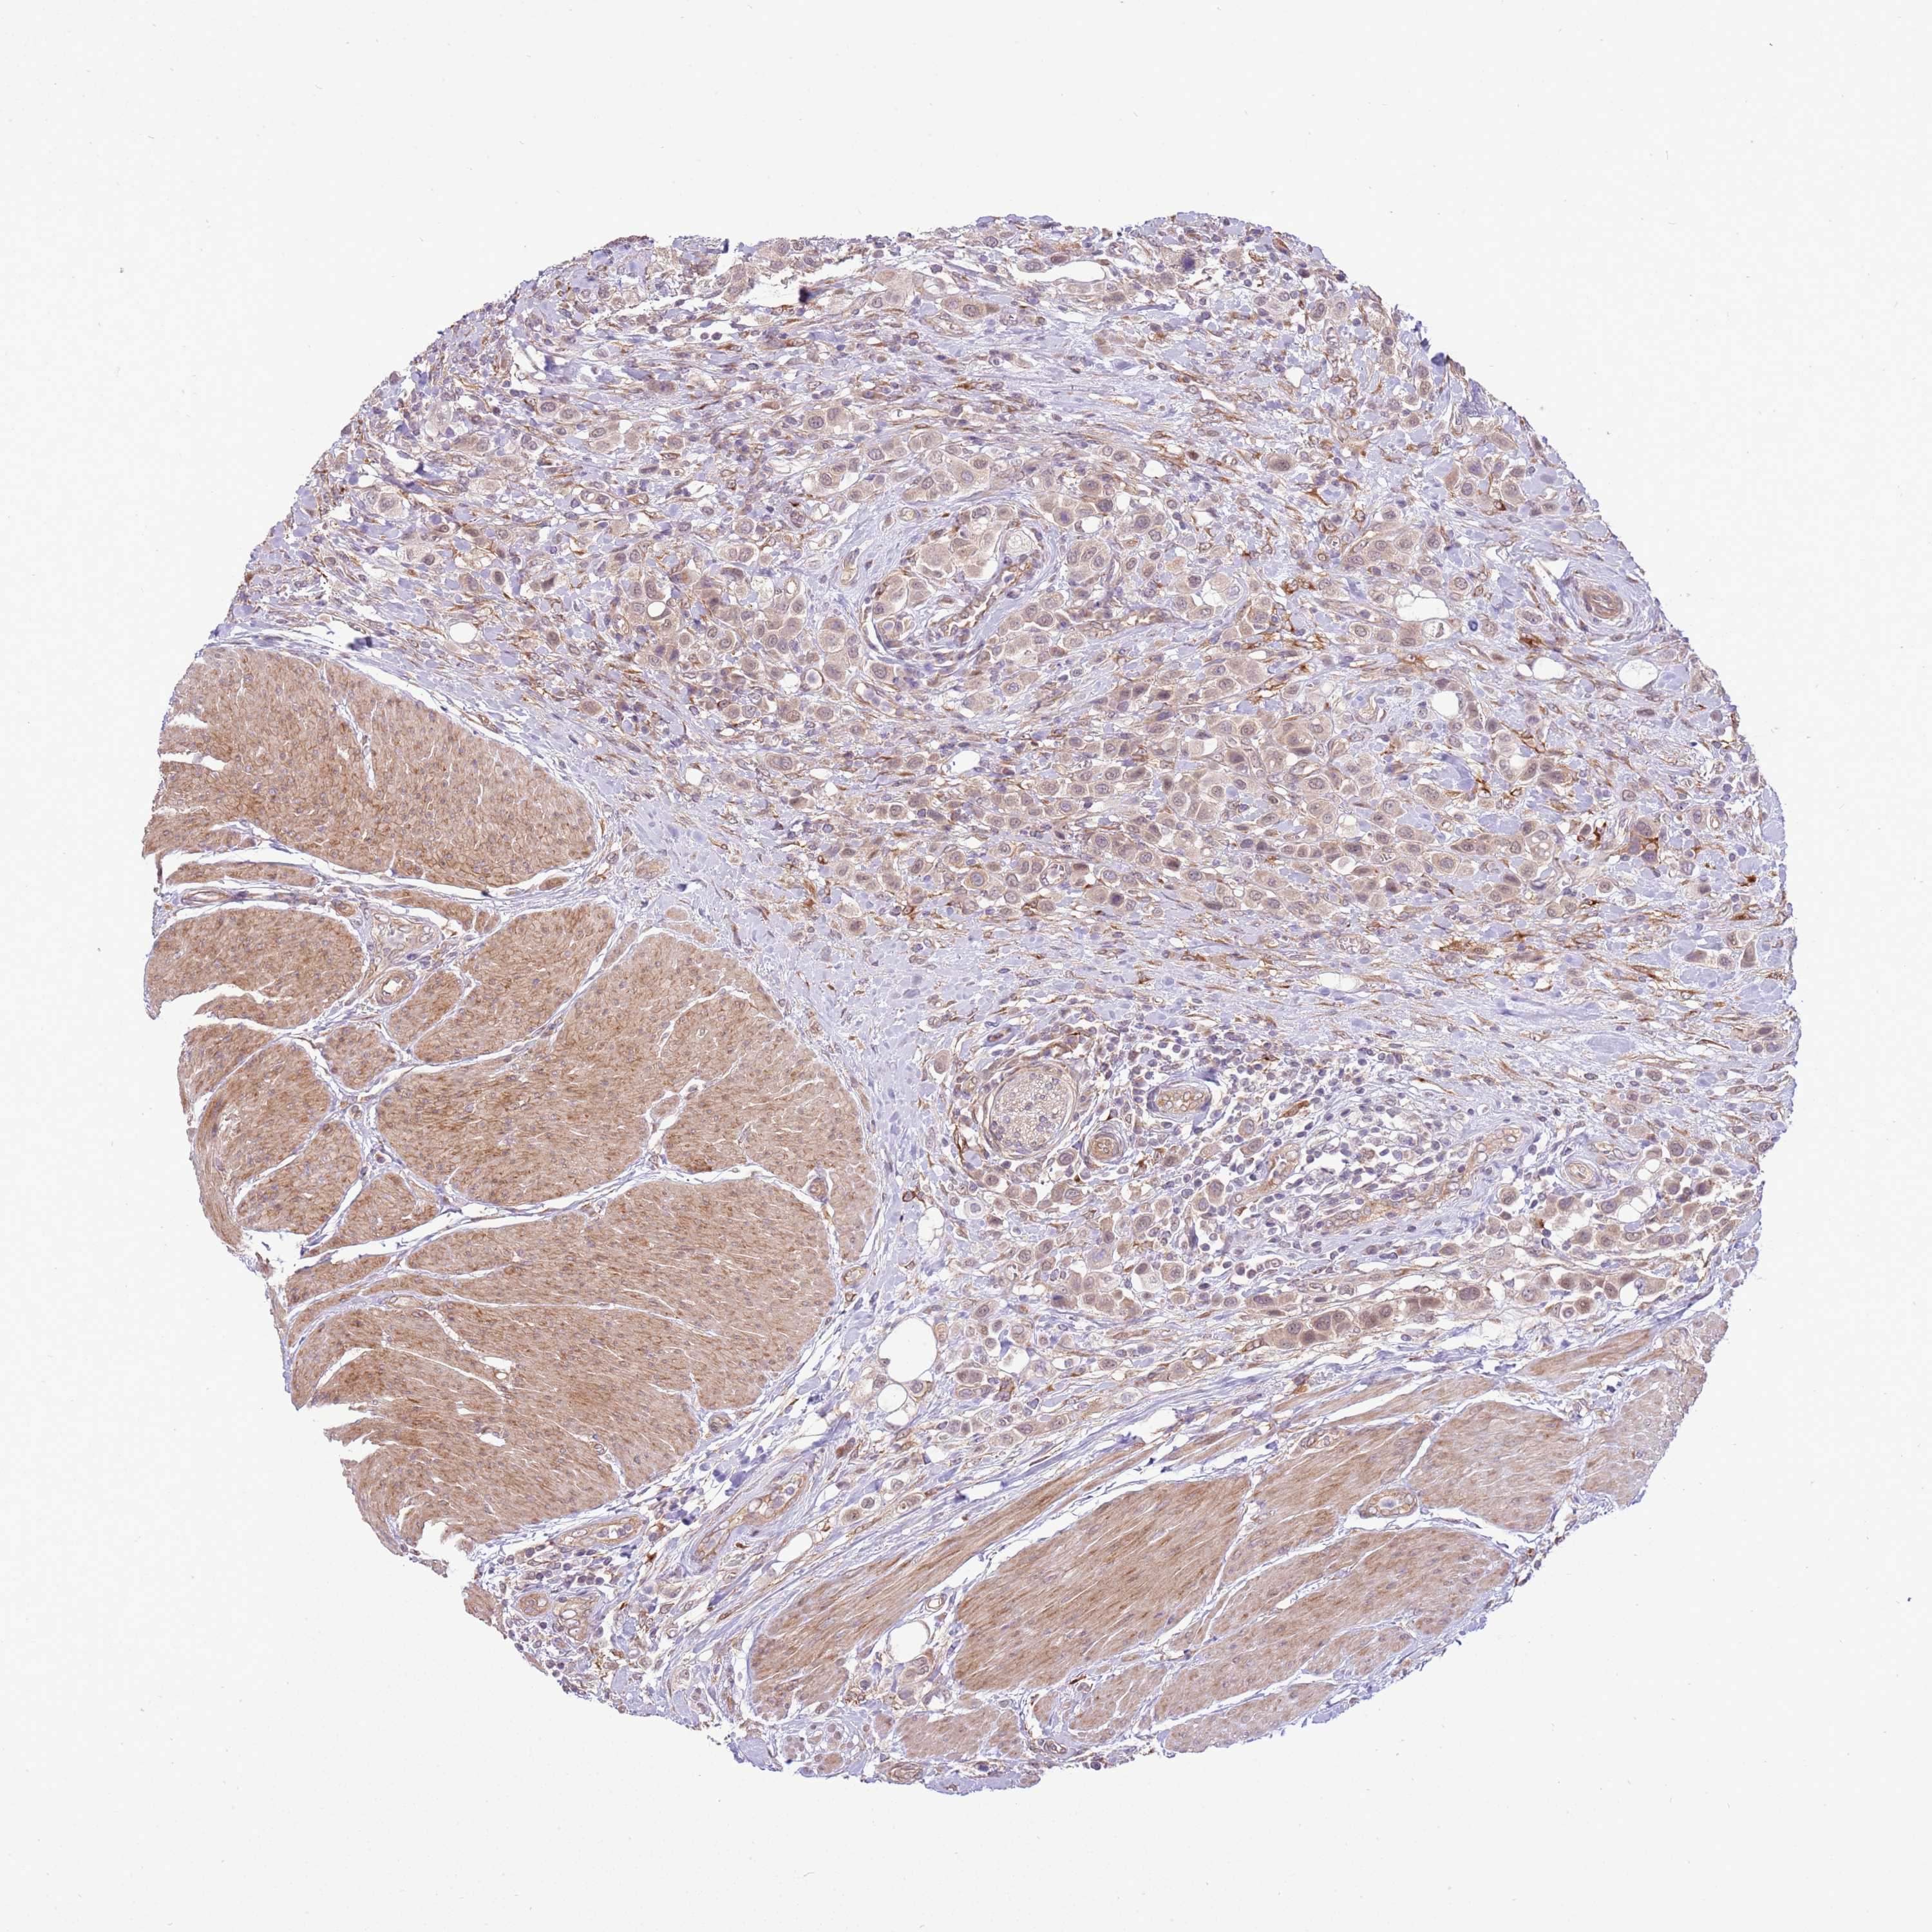

UROTHELIAL CANCER - Protein expressioni

A mouse-over function shows sample information and annotation data. Click on an image to view it in a full screen mode. Samples can be filtered based on level of antibody staining by selecting one or several of the following categories: high, medium, low and not detected. The assay and annotation is described here.

Note that samples used for immunohistochemistry by the Human Protein Atlas do not correspond to samples in the TCGA dataset.

Antibody stainingi

Antibody staining in the annotated cell types in the current human tissue is reported as not detected, low, medium, or high, based on conventional immunohistochemistry profiling in selected tissues. This score is based on the combination of the staining intensity and fraction of stained cells.

Each image is clickable and will lead to virtual microscopy that enables deeper exploration of all samples and also displays staining intensity scores, fraction scores and subcellular localization as well as patient and tissue information for each sample.

Antibody HPA047386

Staining

High

Medium

Low

Not detected

Intensity

Strong

Moderate

Weak

Negative

Quantity

>75%

75%-25%

<25%

None

Location

Nuclear

Cytoplasmic/membranous

Cytoplasmic/membranous,nuclear

Urothelial carcinoma, High grade

Urothelial carcinoma, Low grade